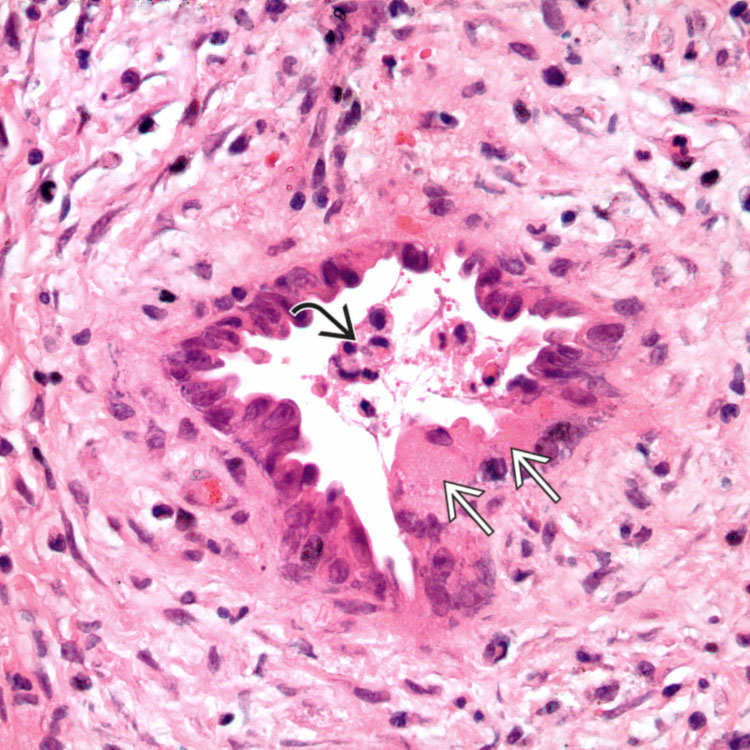

Фотографии и изображения, связанные с симптомами первичного склерозирующего холангита